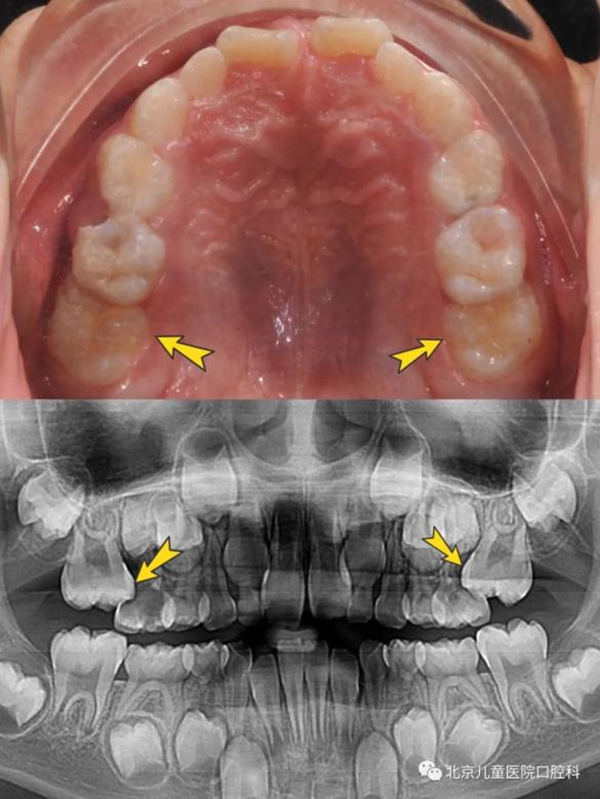

乳牙迟迟没有替换(上图),因为多生牙阻挡(下图)

乳牙是融合牙(上图),对应恒牙牙胚发育异常(下图)

上颌六龄齿卡在前面乳磨牙颈部,位置低,长不出来(上图),六龄齿位置较为隐蔽,萌出时不替换乳牙,萌出障碍很难发现(下图)